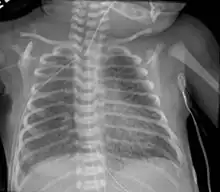

Pulmonary interstitial emphysema

Pulmonary interstitial emphysema is the condition of air escaping overdistended alveoli into the pulmonary interstitium. It is a rare disease that occurs most often in premature infants, even though it is possible to appear in adults.[25] It often presents as a slow deterioration with the need for increased ventilatory support. Chest x-ray is the standard for diagnosis where it is seen as linear or cystic translucencies extending to the edges of the lungs.[9]